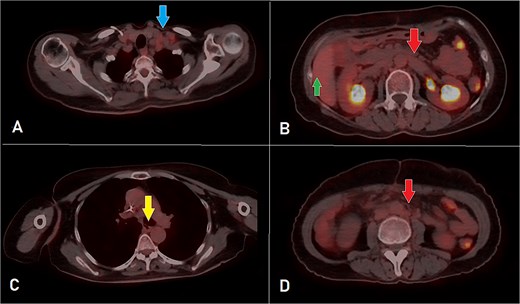

After 8 months of CapeOX-bevacizumab treatment, she was switched to DeGramont-bevacizumab due to neuropathy, receiving seven cycles. The patient later elected to discontinue treatment and was lost to follow-up. Seven months later, she presented with dyspnea on minimal exertion. Laboratory tests were within normal limits; however, a CT scan disclosed a new soft tissue density in the right ventricle, measuring up to 6 cm, suggestive of intracardiac involvement. Imaging findings were consistent with a differential of thrombus versus metastatic lesion. Additionally, filling defects of contrast opacification were observed in the right upper and left lower segmental and subsegmental pulmonary artery branches, indicative of concurrent pulmonary embolisms. A new right external iliac lymph node enlargement was also identified. The overall clinical and radiological assessment was consistent with disease progression (Fig. 3).

A, B, and C displaying the baseline images. (D) A mass lesion originating from the right ventricle (arrow). (E) Filling defect in the segmental branches of the pulmonary artery representing pulmonary embolism (arrow). (F) A newly seen right para-iliac lymph node (arrow).